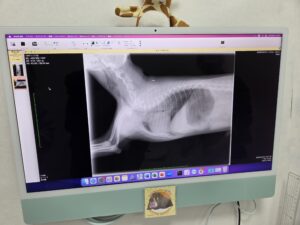

救急患者🐶

我が家のワンchannが急に咳き込み・呼吸が苦しそうだったので急遽動物病院を受診しました。呼気が長くかつ喘鳴聴取するので下気道に問題ありそうです。酸素投与、ステロイドに拡張剤受け帰宅しました。少し元気になりましたが、冷静に経過見るのみです。妻はテンパっておりました。😅